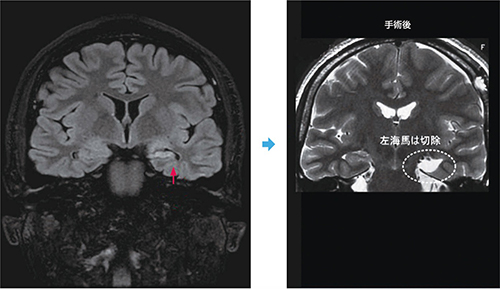

また「内側側頭葉てんかん」など難治てんかんの種類によっては、手術が奏功することが知られており、このような場合は、薬物療法にこだわって時期を逸することなく、手術治療を行うことをお勧めします(画像)。

画像 症例に提示した患者さんの頭部MRI-FLAIR画像冠状断:左海馬硬化症を認める(左↑)。画像で左海馬部分は対側に比べ小さめで色調が違います。手術後、同じ部分は摘出しました(右)